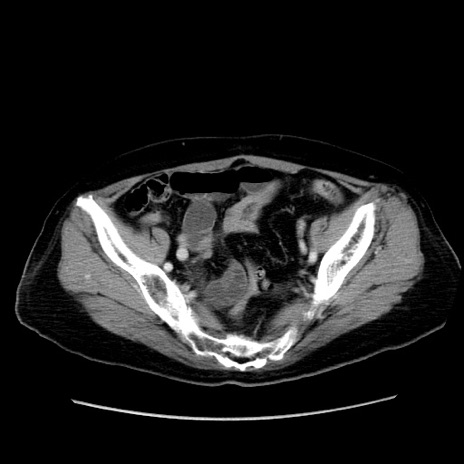

冠状断像

症例19(横断像)

【症例】80歳代女性

【主訴】下腹部痛

【現病歴】約8時間前より下腹部痛の出現あり、救急外来受診。

【既往歴】両側付属器切除

【身体所見】意識清明、下腹部正中に手術痕あり、その部位に一致して圧痛と反跳痛あり。腸蠕動音は亢進。

【データ】WBC 9300、CRP 0.15